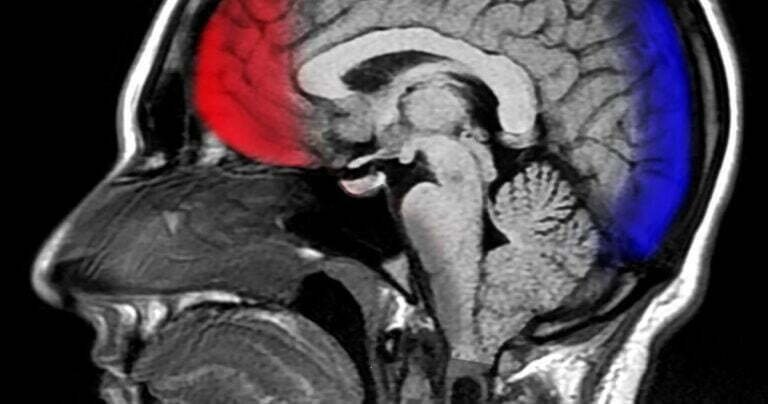

Le cerveau humain est le centre de commande du système nerveux humain. Il est l’un des organes…